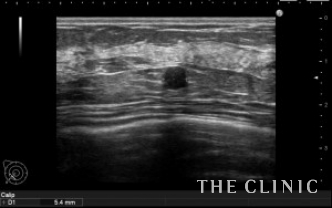

本日は他院で行った脂肪豊胸後のしこりの治療を行いました。

エコーでは充実性成分を含むしこりで、被膜の石灰化ははっきりしません。

小さなオイルシストも認めます。